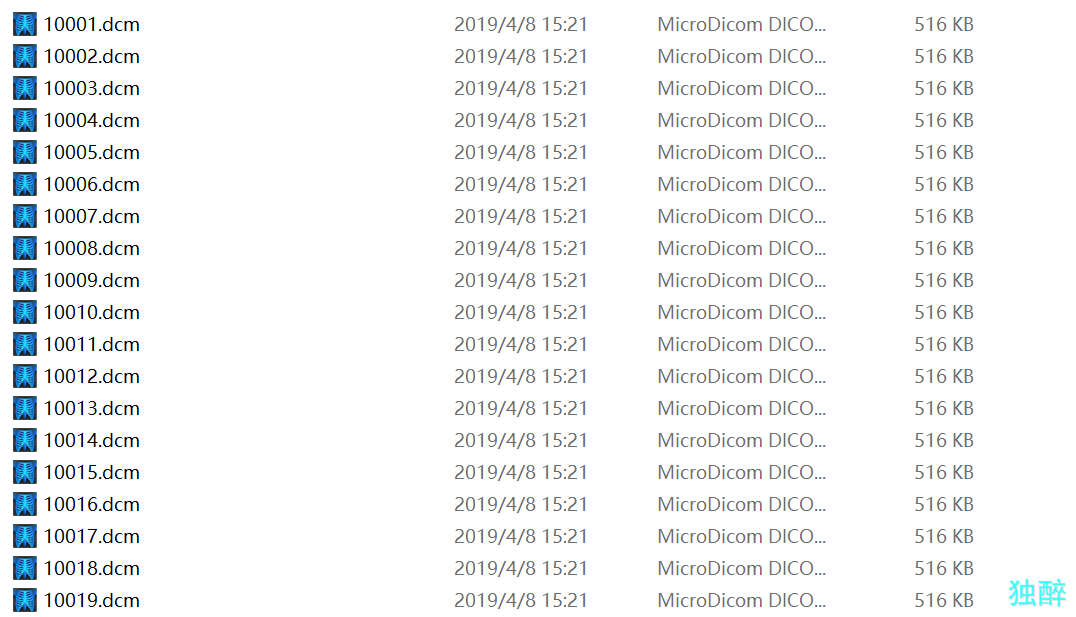

这是CT图的文件夹,都为dcm文件

这是CT图的文件夹,都为dcm文件